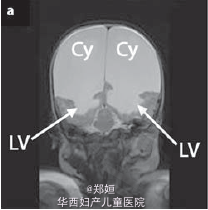

复查超声,提示存活的胎儿脑皮质变薄,怀疑脑穿孔 孕28周MRI检查提示脑穿孔性囊肿 孕41周自然生产3.1kg女婴 胎盘肉眼可见死亡的一胎紧贴胎盘 胎儿MRI提示双侧脑实质局灶性损害 MR造影提示双侧的大脑中动脉阻塞

胎儿之后出现智力障碍,并有West综合征